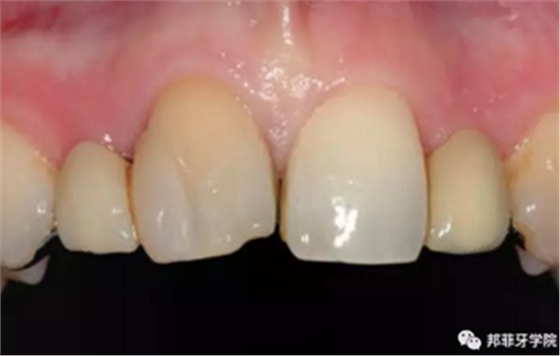

26歲女性患者,雙側(cè)上頜側(cè)切牙先天缺失,對(duì)原有修復(fù)體的“形態(tài)”、“光澤”等方面不滿意,希望重新修復(fù)(圖1&2)。12及22原為粘接橋修復(fù),11根管治療史;拆除原修復(fù)體后余鄰牙完整,未見病理性探診深度。無系統(tǒng)疾病史。患者期望值較高,告知治療流程佩戴臨時(shí)卡環(huán)義齒等(圖3)、費(fèi)用、風(fēng)險(xiǎn)后表示接受治療。

圖1:治療前口內(nèi)情況

圖2:治療前全景片